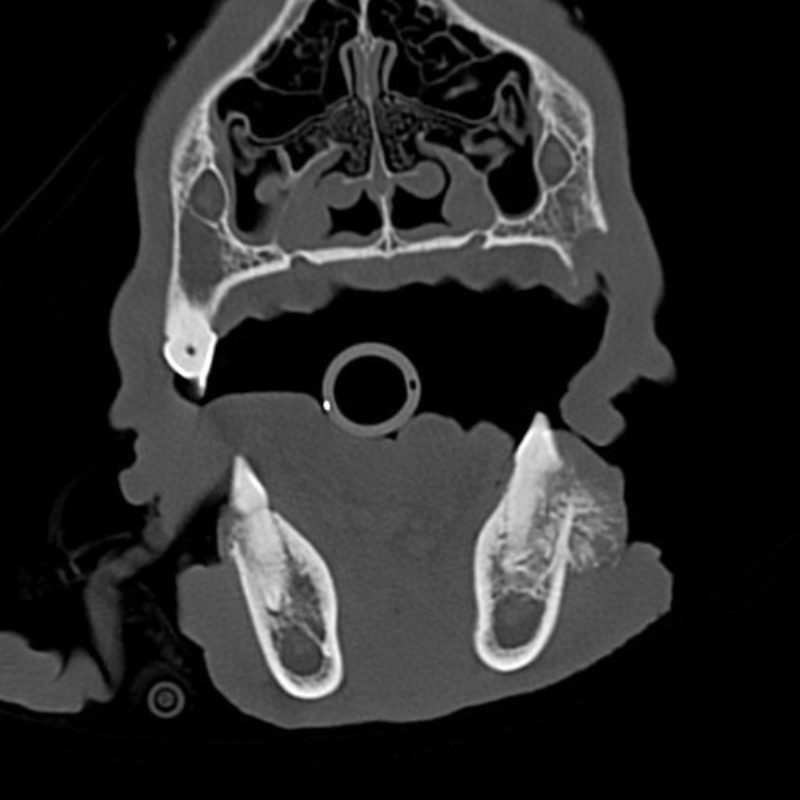

Die Heilungsaussichten sind sehr gut, wenn der Tumor vollständig mit dem Zahnhalteapparat entfernt wird. Es ist nicht erforderlich, extrem viel Gewebe um den Tumor herum zu entfernen. Die genauen Operationsgrenzen wurden vor der Operation durch eine Computertomographie bestimmt. Dieses Verfahren lässt die Knochenstruktur sehr gut erkennen. So lässt sich sehr viel genauer als mit einem Röntgenbild beurteilen, wie weit die Veränderung reicht. Der Tumor lässt sich anhand dieses Befundes komplett entfernen.

Die Besitzerin des Patienten legte viel Wert auf die Erhaltung von möglichst viel gesundem Gewebe. Der vordere Bereich mit Eckzahn und Schneidezähnen, zwei Backenzähne und das Kiefergelenk sollten geschont werden. Es wurde eine Teilresektion des Unterkiefers vorgenommen. Das betroffene Gewebe wurde entfernt und in die Pathologie geschickt. Der Befund zeigte, dass sich die Operationsgrenzen im gesunden Gewebe befanden.